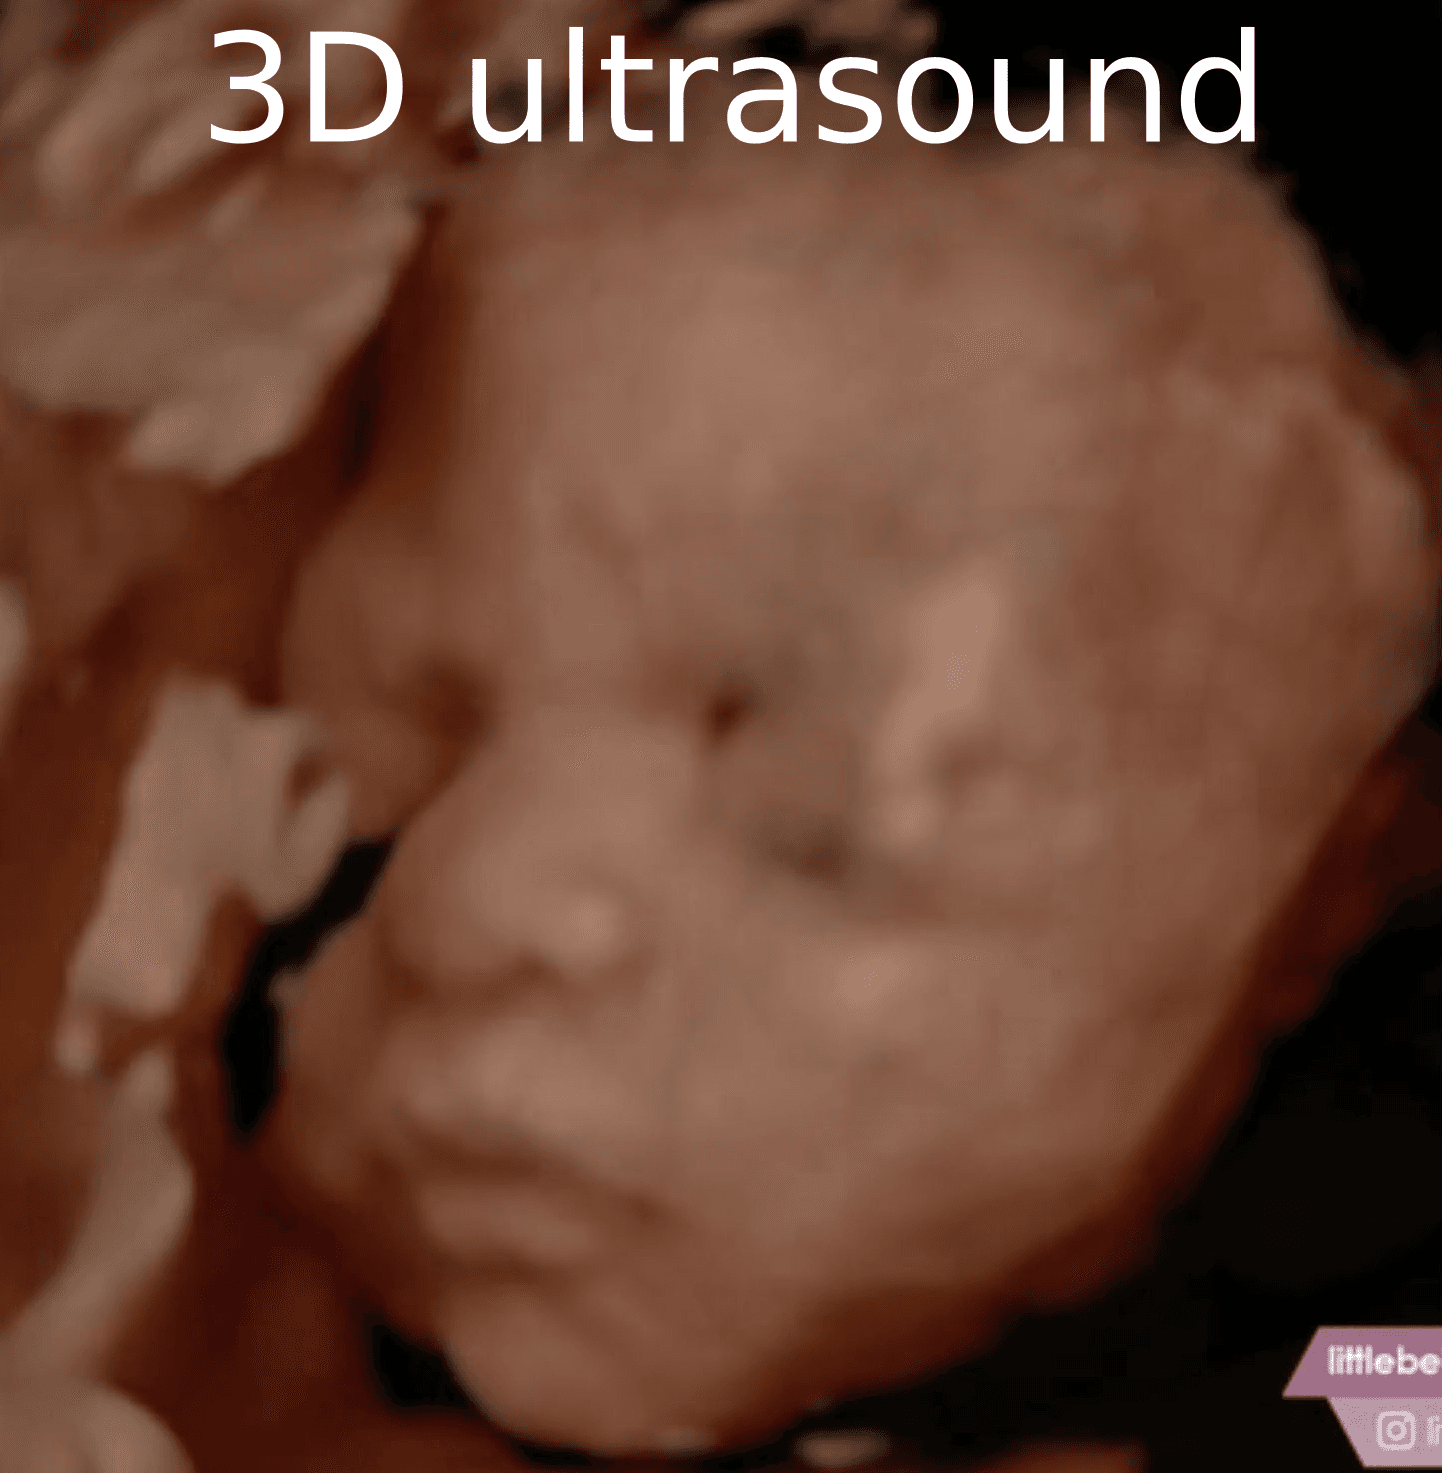

Tap a clip to play an animated ultrasound example.

Simply upload your 3D ultrasound image and proceed from there. Our system will guide you through the enhancement process step by step.